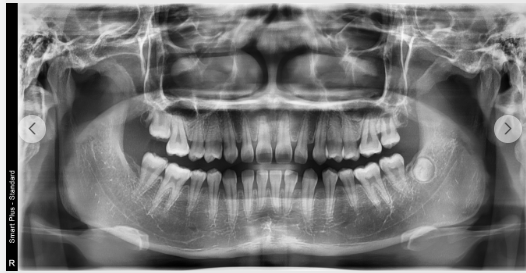

(부정교합 교정 치료 전(위)/후(아래))